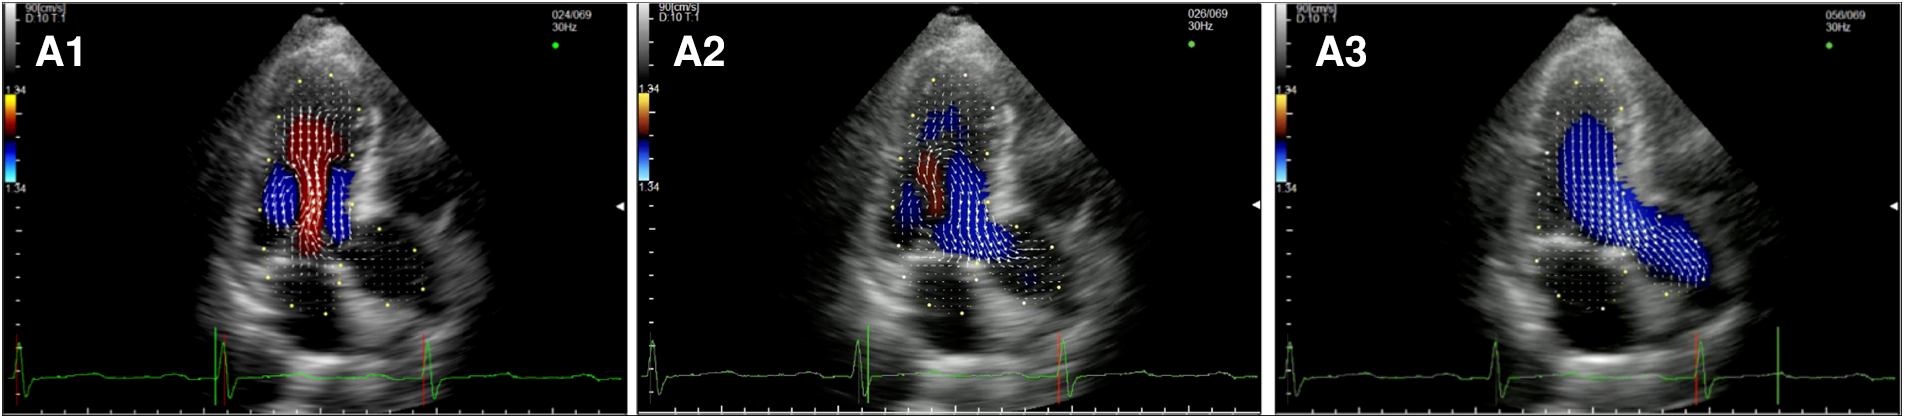

In the healthy controls (Figure 1, panel A1,A2,A3, Supplementary Video S1), blood enters the LV cavity through the MV smoothly, creating two vortices that move in opposite directions, a main clockwise vortex beneath the AML and a smaller counterclockwise vortex beneath the PML. While the posterior vortex dissipates quickly, the anterior vortex keeps getting bigger during diastole moving downstream and pushing the blood flow towards the posterior wall of the LV and then redirecting the flow towards the LVOT during systole. In systole, hemodynamic forces are directed mainly along the left ventricle longitudinal axis, from the apex to the LVOT, without significant vortices (i.e., vortices that persist for at least two consecutive frames).

Figure 1

Apical long-axis view. Intracardiac flow vectors in early diastole (A1–C1) and late diastole (A2–C2) for control patient, patient with DMR and patient with FMR respectively; intracardiac flow vectors in mid-systole for control patient (A3), patient with DMR (B3) and patient with FMR (C3).

In patients with DMR (Figure 1, panel B1,B2,B3, Supplementary Video S2),the diastolic flow pattern composed ofthe two LV vortices is preserved. However, during late diastole and early systole, the anterior vortex does not direct the flow toward the LVOT because the hemodynamic forces are directed from the apex to both the LVOT and the left atrium due to the posterior leaflet prolapse, leading to the formation of multiple vortices proximal to the MV (mainly with a clockwise rotation). In FMR (Figure 1 panel C1,C2,C3, Supplementary Video S3), we observed only one clockwise vortex distal to the AML during early filling. In systole, because of PML tethering causing MV malcoaptation, hemodynamic forces are directed from the apex both to the LVOT and to the left atrium leading to the formation of a counterclockwise vortex proximal to the MV.